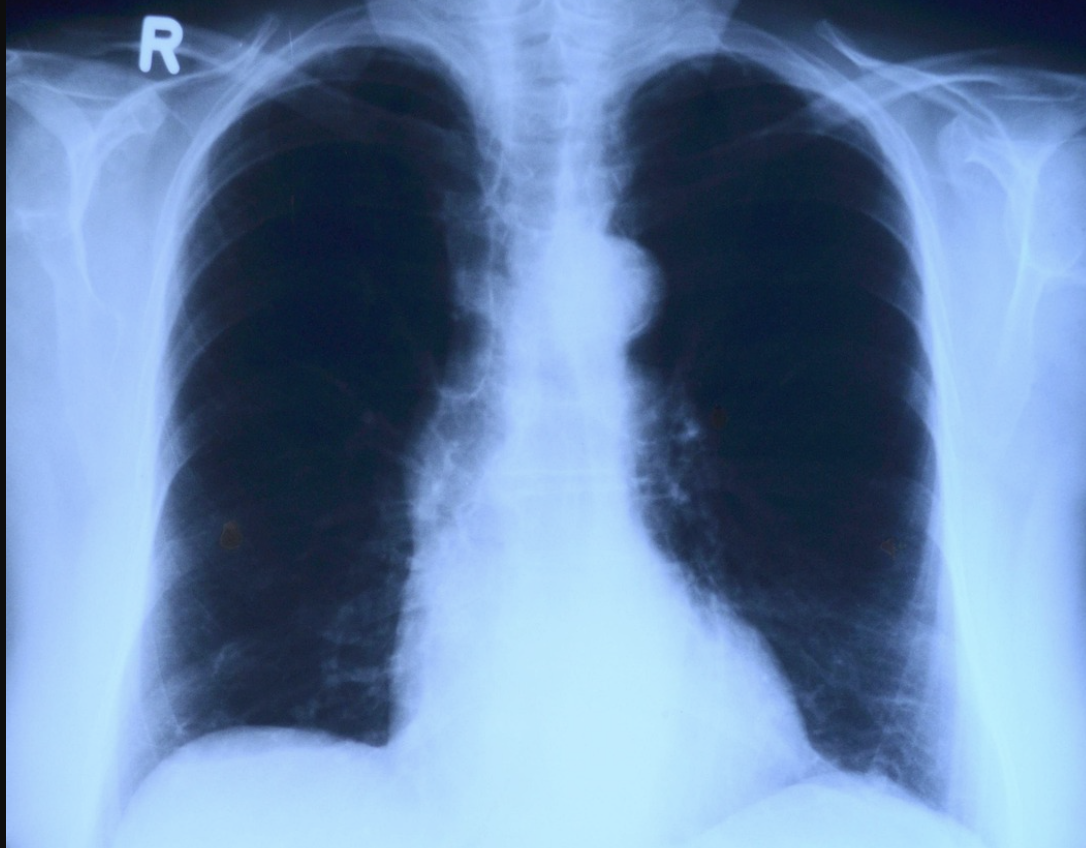

Мужчины в Красноярском крае чаще других в Сибири сталкиваются с раком лёгких. Об этом рассказала старший научный сотрудник отделения торакальной онкологии НИИ онкологии Томского НИМЦ Татьяна Полищук. По её словам, самые высокие показатели заболеваемости среди мужчин зафиксированы в Алтайском и Красноярском краях, при этом в последнем отмечается и высокий уровень смертности.

По данным онкодиспансеров, только за прошлый год в каждом из этих регионов выявили более 1000 случаев рака лёгких. Медики напоминают, что на ранних стадиях болезнь обычно не проявляется, из-за чего пациенты часто обращаются за помощью слишком поздно. В Сибири рак лёгких удаётся диагностировать на ранних стадиях примерно в 35% случаев, тогда как почти треть пациентов узнают о болезни уже на последней стадии, а в отдельных регионах этот показатель достигает 45%.

К основным факторам риска врачи относят курение, хронические болезни дыхательных путей, вредные условия труда и плохую экологию. В последние годы специалисты отмечают рост числа заболевших и среди женщин, что, по мнению Полищук, может быть связано с распространением вейпов и электронных сигарет.

По информации краевого минздрава, в 2023 году рак лёгких диагностировали у 1401 жителя региона. Мужчины болеют значительно чаще, а средний возраст заболевших снизился с 60 до 47–50 лет.

Всего в 2024 году в Красноярском крае на учёте состояли 82 508 человек с онкологическими заболеваниями, среди них около 500 детей. От рака в регионе за год умерли 6040 человек, что составляет 212,6 случая на 100 тысяч населения. При этом за последние десять лет смертность от онкологических заболеваний снизилась почти на 22%.